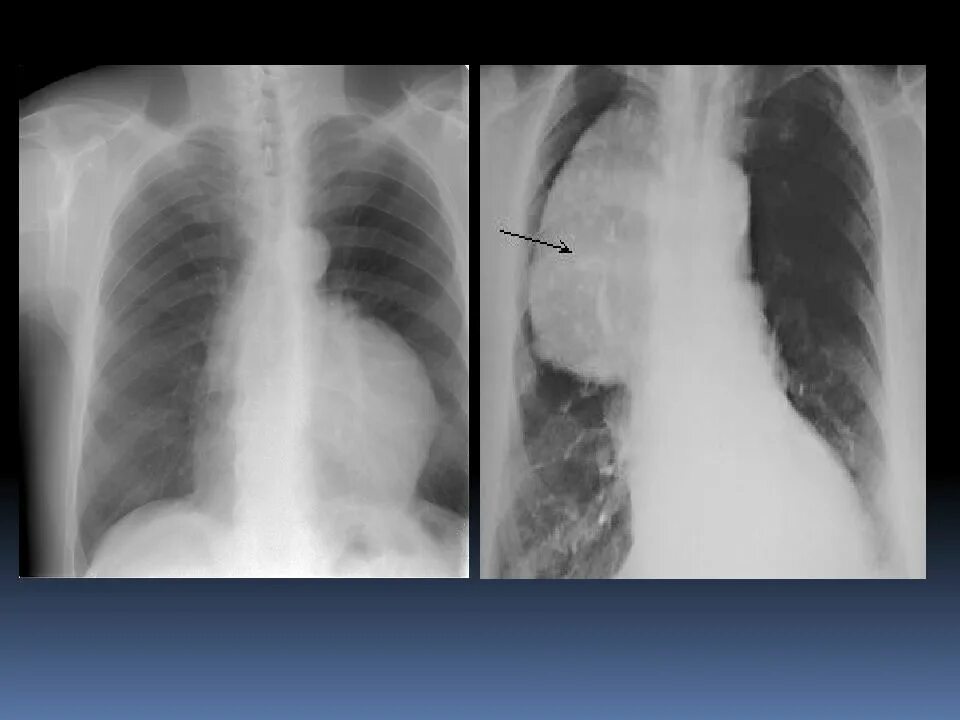

Тимус в переднем средостении